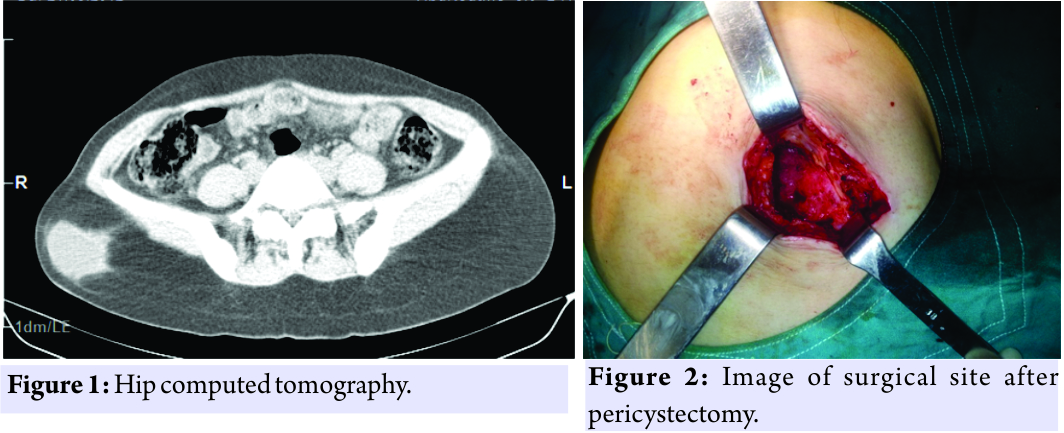

A 36-year-old woman affected by pain and a mass in her right gluteal region with a 2-year history was seen in outpatient clinic. She suffered from pain growing by walking and limited hip motion. Her examination revealed a mild erythema and a small swelling in contrast to her contralateral hip in gluteal region. In history, she was misdiagnosed in another center as having an abscess diagnosis and needle aspiration was made by local clinician. No pathological findings were seen radiolographies. Her serological test results were normal. Ultrasonography (USG) revealed a 52 mm × 47 mm diameter hypoechoic intramuscular cyst with septations. Computed tomography (CT) demonstrated a cystic lesion located in posterior muscle groups and extending inferiorly without bony involvement (Fig. 1). The findings were interpreted as hydatid cysts. The echinococcal indirect hemagglutination test (IHA) was found to be negative. However, this result was evaluated as false negative. Additional examinations were performed with the consideration that may be a tumor. No pathological findings were observed in abdominal USG and thoracic CT. She was operated under spinal anesthesia. A 5-cm diameter well-demarcated mass was found over the gluteal muscle tissue. Affected area was irrigated with povidone-iodine (betadine) for 5 minutes. Cyst was excised entirely. Surgical site was washed with hypertonic saline (Fig. 2). Later, the mass was intentionally ruptured, odorless, clear fluid, and daughter vesicles were observed. Biopsy was taken. Postoperatively, albendazole chemotherapy was prescribed. Biopsy was reported hydatid cyst as chitinous cuticular membrane and inflammation in the surrounding tissue (Fig. 3). She had no complaints at her latest follow-up.

The findings were interpreted as hydatid cysts. The echinococcal indirect hemagglutination test (IHA) was found to be negative. However, this result was evaluated as false negative. Additional examinations were performed with the consideration that may be a tumor. No pathological findings were observed in abdominal USG and thoracic CT. She was operated under spinal anesthesia. A 5-cm diameter well-demarcated mass was found over the gluteal muscle tissue. Affected area was irrigated with povidone-iodine (betadine) for 5 minutes. Cyst was excised entirely. Surgical site was washed with hypertonic saline (Fig. 2). Later, the mass was intentionally ruptured, odorless, clear fluid, and daughter vesicles were observed. Biopsy was taken. Postoperatively, albendazole chemotherapy was prescribed. Biopsy was reported hydatid cyst as chitinous cuticular membrane and inflammation in the surrounding tissue (Fig. 3). She had no complaints at her latest follow-up.